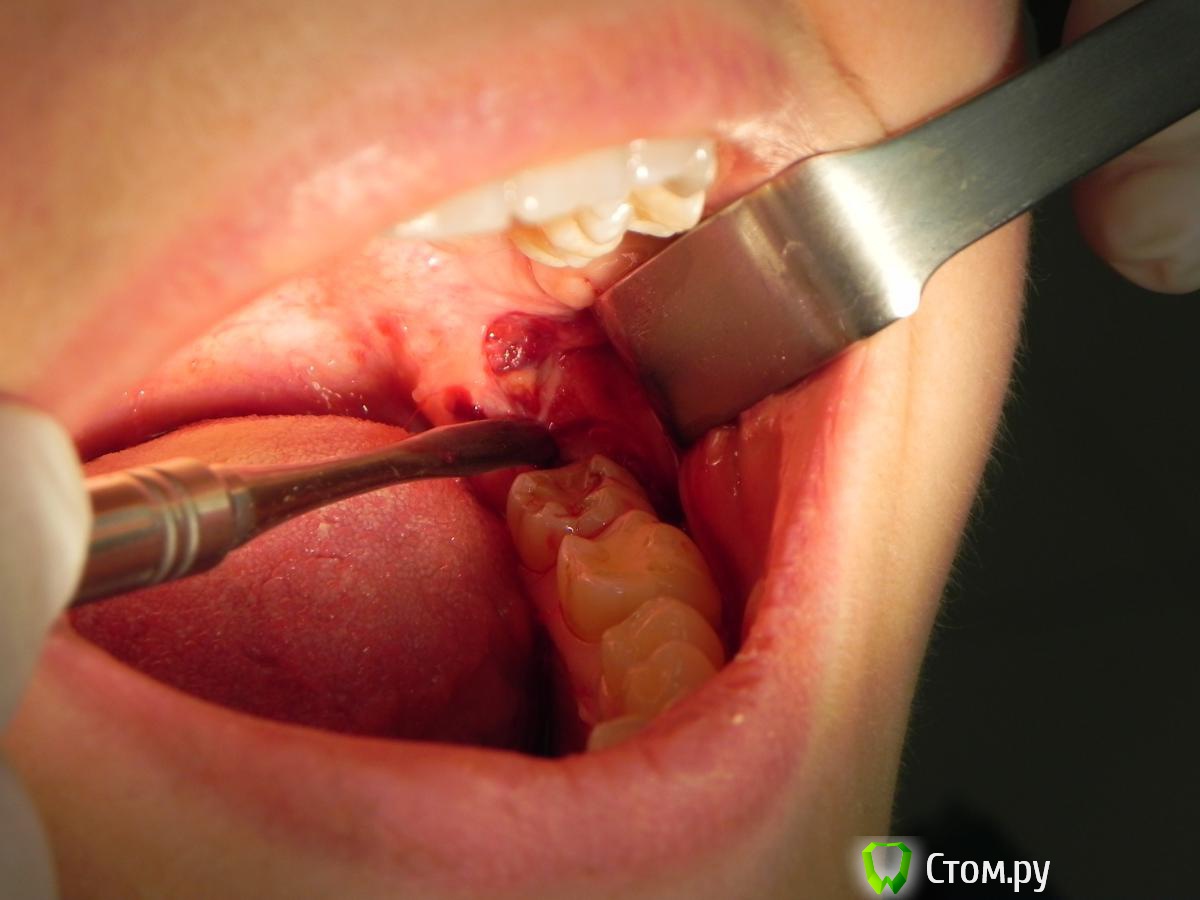

Kostoprav Опубликовано 10 июня, 2014 Поделиться Опубликовано 10 июня, 2014 вот такой клад откопал недавно) 2 Ссылка на комментарий

IvanK Опубликовано 11 июня, 2014 Автор Поделиться Опубликовано 11 июня, 2014 @Kostoprav, слюна не очень симпатично смотрится.. попробуйте пользоваться миниссотом+ обрезать бы фото ) очень удобно с оптрагейтом Ссылка на комментарий

red_butler Опубликовано 11 июня, 2014 Поделиться Опубликовано 11 июня, 2014 вот такой клад откопал недавно) Почему зуб не сегментировали? 1 Ссылка на комментарий

Kostoprav Опубликовано 11 июня, 2014 Поделиться Опубликовано 11 июня, 2014 (изменено) Почему зуб не сегментировали?Стараюсь не сегментировать дабы рану не засорять "зубным мусором" + наблюдал случаи когда не хилые эмфиземы надували. Хотя бывало приходилось прибегать к этому методу ) Изменено 11 июня, 2014 пользователем Kostoprav Ссылка на комментарий